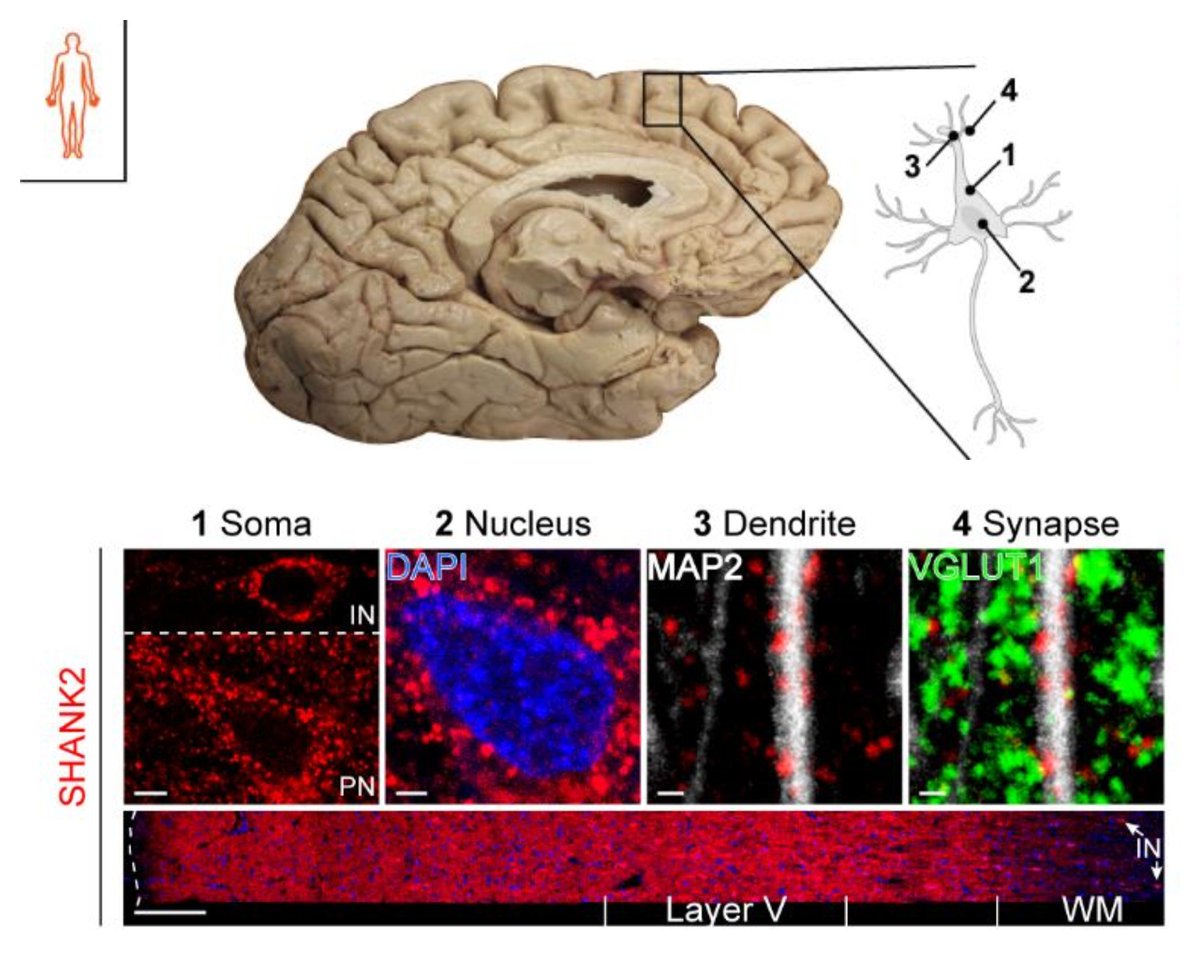

📚 New paper alert! 🎉 We are excited to announce the new publication in Acta Neuropathologica! 🧠🔬 This collaborative effort with the group of Chris Henstridge (University of Dundee ) has led to groundbreaking discoveries in the field of ALS research. link.springer.com/article/10.100…